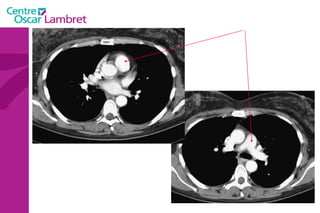

L’appareil circulatoire L’appareil circulatoire  s’appuie sur un véritable réseau aussi étendu que précis. Sous l’impulsion du  coeur , chef d’orchestre vital, les artères et les veines assurent le transport du sang indispensable à tout notre organisme.  Les artères  apportent le sang riche en oxygène et en nutriments à l’ensemble des tissus de l’organisme.  Les veines  doivent rapporter le sang appauvri en oxygène vers le coeur puis les poumons. Des  poumons , il repasse dans le coeur qui le propulse de nouveau via les artères à tout l’organisme.

Le cœur  se situe au milieu du thorax, sur le diaphragme, la pointe tournée vers la gauche. L’appareil circulatoire

Le coeur  comprend quatre cavités :  deux cavités droites, formées par l’oreillette (ou atrium) et le ventricule droit.  deux cavités gauches, formées par l’oreillette (ou atrium) et le ventricule gauche.  Les cavités droite et gauche sont totalement séparées par une cloison (septum).  Ces cavités sont connectées à des veines et des artères qui conduisent le sang venant ou partant du coeur.  L’appareil circulatoire

Les 2  atriums  ont un petit diverticule : les auricules Le cœur repose sur le diaphragme et est situé au niveau de la partie antérieure et inférieure du médiastin. Le coeur est bordé latéralement par les poumons qui le recouvre partiellement. Les 4 cavités du coeur sont limitées par des sillons. Le  sillon coronaire le sillon inter atrial  Le sillon inter ventriculaire ou septum L’appareil circulatoire

L’appareil circulatoire L’ aorte  est la plus grande artère du corps.  Elle part du ventricule gauche du coeur et apporte notamment du sang oxygéné à toutes les parties du corps via la circulation. Elle est divisée en aorte thoracique et aorte abdominale. L’aorte thoracique  comprend trois segments : l'aorte ascendante, horizontale et descendante.